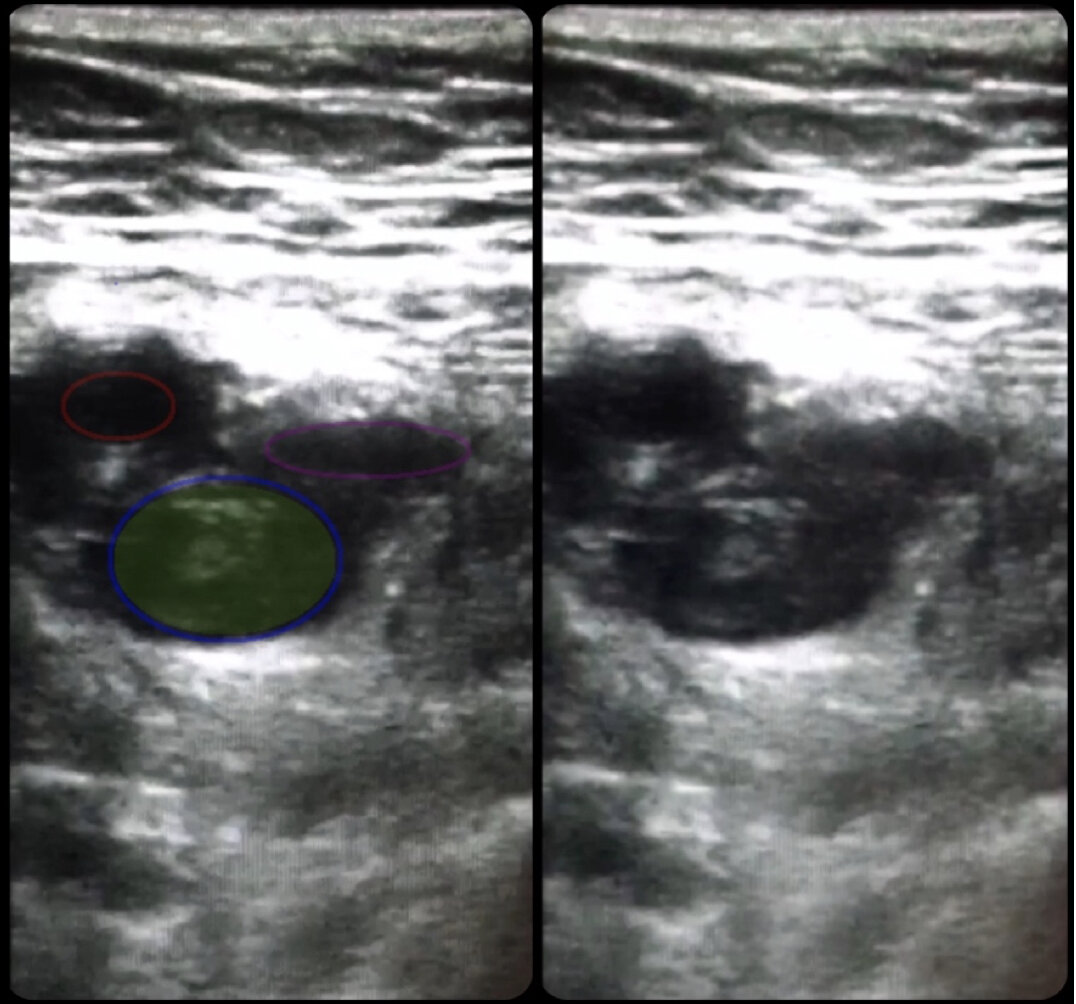

УЗИ вен: метод визуализации, при котором используются звуковые волны для создания изображений крови. Методика позволяет увидеть, есть ли тромбы в венах.